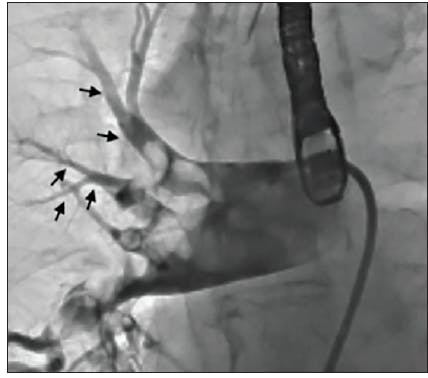

The initial angiogram confirmed an occlusion with extensive thrombus burden of a dominant left circumflex artery and TIMI 0 flow (Figure 1). Power aspiration with CAT RX and Penumbra ENGINE was started after wiring the dominant left circumflex artery. After one pass with CAT RX, the initial occlusion was removed. A second angiogram showed extensive clot burden spread across multiple branches (Figure 2). Each vessel was wired sequentially, delivering power aspiration via CAT RX to the site of each thrombus. A final angiogram revealed complete reperfusion to the dominant left circumflex artery and branches, with TIMI 3 flow (Figure 3).